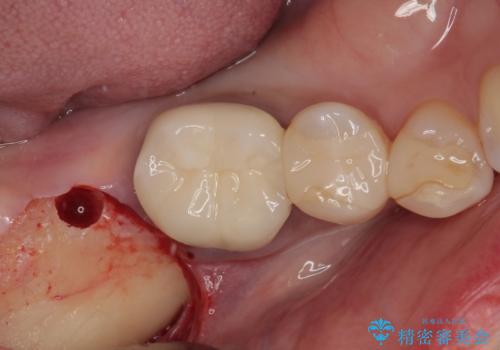

放置した奥歯 部分矯正を併用したインプラント補綴治療

- 右下欠損部のインプラント治療を希望して来院された患者様です。

右下の欠損部を長期間欠損を放置していたことで、咬み合う上の奥歯が動いてしまっていたので、まずは上顎奥歯の部分矯正を行うこととしました。

理想的な咬み合わせに改善した上で、インプラント補綴治療を行うこととしました。

部分矯正を行ったこと治療期間は長くなりましたが、違和感のない咬み合わせを達成することができました。